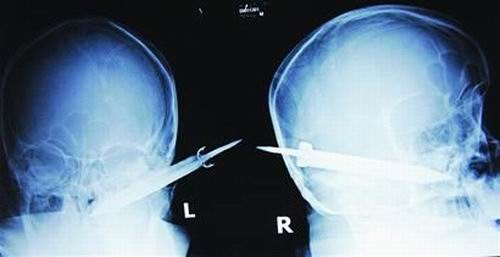

經過檢查,醫生說這把長有10厘米左右的刀,從右耳窩上前方直接刺進了鼻腔,離頜內大動脈很近,刀卡在了骨頭中,要取出這把刀最怕大出血,萬幸的是這把三棱刀并沒有傷及大腦。

截至昨晚11時30分,患者頭部刀經手術已取出,生命體征平穩。(芮瀟瀟)